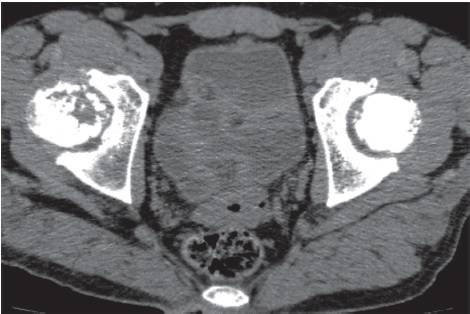

Upon admission, there were no visual signs of swelling or redness of the skin in the area of the hip joints. On palpation, there was local and axial tenderness in the projection of the right femoral head. The range of motion in the right hip joint was limited — external abduction 10°. Pain on the VAS was 5-6 points. The left hip joint was painless, with a full range of motion. There was a shortening of the right lower extremity by 2.0 cm. X-rays and CT scans showed signs of bilateral aseptic necrosis of the femoral heads, more pronounced on the right — stage 3B-4 according to ARCO (Fig. 4, 5). In blood tests, the ESR was accelerated to 58 mm/hr., other results were within reference values.

Fig. 4. Clinical case 2. CT scan of the pelvis, axial reconstruction — bilateral osteonecrosis of the femoral heads: right — stage 3B (late) according to ARCO, left — stage 3A (early) according to ARCO